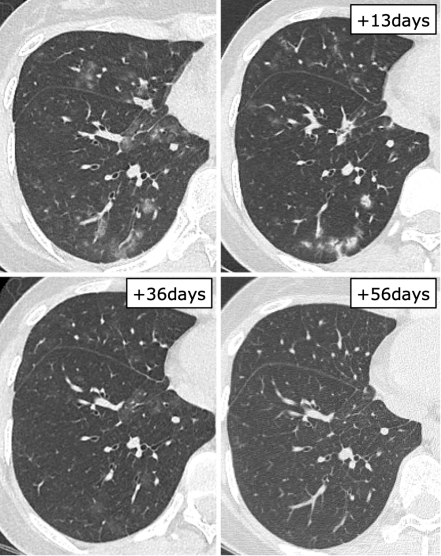

日本一项研究总结了血液系统疾病和造血干细胞移植患者RSV感染的影像学表现,其中一例63岁T淋巴细胞瘤患者感染RSV后症状持续10天,右肺下叶支气管处支气管管壁增厚,经过治疗,情况有所改善(图1)。图2为一例75岁T细胞淋巴瘤患者,起病9天,肺上叶可见小叶中心结节影(图2)。23岁急性粒细胞白血病患者早期影像学表现为多叶段沿支气管束分布的磨玻璃影,随着时间的延长以及治疗的开展,病变密度逐渐增加、皱缩及吸收(图3)。图4为一例78岁慢粒患者,羟基脲治疗,起病1天,影像学可见铺路石征,随着时间的延长,逐渐吸收(图4)

图片

图4  78岁慢粒患者患者感染RSV的影像学表现

图源:Intern Med. 2020;59(2):247-252.